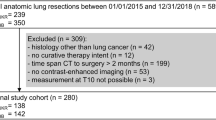

This is a single centre, ethics approved (2019/ETH13149), retrospective study of all adult (≥ 18 years) patients with a confirmed newly diagnosed squamous cell HNC, who presented to a tertiary referral Hospital in Sydney, Australia between January 2013 and June 2021.

All patients who presented with HNC of the larynx, hypopharynx, nasopharynx, oropharynx, or oral cavity, and had a baseline diagnostic positron emission tomography–computed tomography (PET–CT) scan were included. PET–CTs only were used as both the L3 and C3 landmarks are accessible for evaluation. Exclusion criteria were: patients who had a previous cancer diagnosis or had received any treatment (e.g., radiotherapy, chemotherapy or cancer-related surgery), or those who had incomplete or unclear PET–CT scans. Height and weight were recorded at the time of initial consult and collected from patient medical records, measured within 2 weeks of having the scan.

There were 116 PET–CT scans (of 116 patients), of which seven were deemed ineligible. Three patients had unclear scans of the C3 landmark due to extensive neck curvature, three patients had incomplete scans that did not include the L3 landmark, and one patient had a late diagnosis that was not carcinoma. A total of 109 patient PET–CT scans were analysed that included both L3 and C3. The majority were male (85%) with a mean (SD) age of 61 (± 10.4) years. Most presented with squamous cell carcinoma of the oropharynx (69%) and T1 stage disease (37%). The median BMI of the cohort was 27 kg/m2, and 64% had a BMI ≥ 25 kg/m2. Detailed patient characteristics are shown in Table 1.